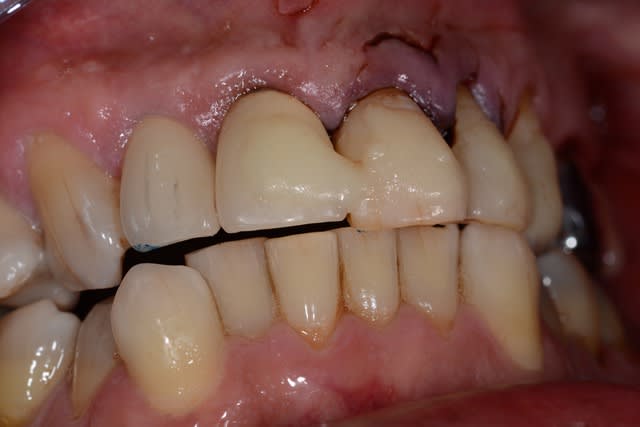

Ne jamais provoquer quelqu'un qui tient un marteau dans sa main !

Putain j'ai mal pour lui juste en regardant la photo.